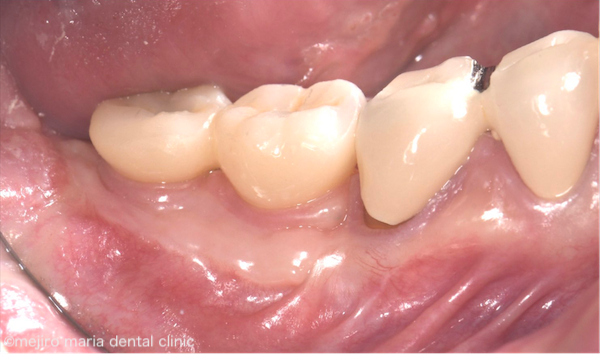

治療後の様子

目白マリア歯科|歯周形成外科の症例|インプラントを守るための歯茎の移植(FGG)|治療後の歯茎の画像

術後3ヶ月後で歯肉の再生が達成され、安定しています。インプラントの上物も装着されていますが、患者様は痛みもなく適切にブラッシングできています。この状態ならば、ご自身のケアと定期的なメンテナンスでインプラントは長持ちするでしょう。